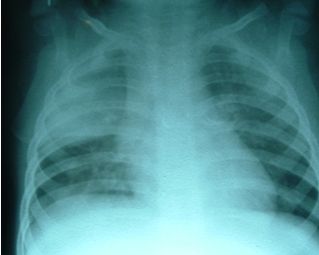

La neumonía alveolar (también denominada lobar, lobular o neumonía segmentaria) es en general causada por patógenos bacterianos, y Streptococcus pneumoniae en particular, sobre todo cuando se acompaña de recuento elevado de leucocitos periféricos, las concentraciones de proteína C reactiva (PCR) y fiebre alta, lo que justifica el tratamiento con antibióticos.

Según comentan los autores, Greenberg y col. 2013,  ningún estudio hasta la fecha ha utilizado una combinación de signos clínicos, hallazgos de laboratorio y la definición de la radiografía de tórax, para comparar la duración del tratamiento ambulatorio oral en la NAC  alveolar, en la infancia.

Para aumentar la probabilidad diagnostica de neumonía bacteriana, y minimizar la variabilidad entre los pacientes, se utilizaron criterios de selección predefinidos, que incluían radiografía de tórax, la temperatura corporal y hallazgos de laboratorio.